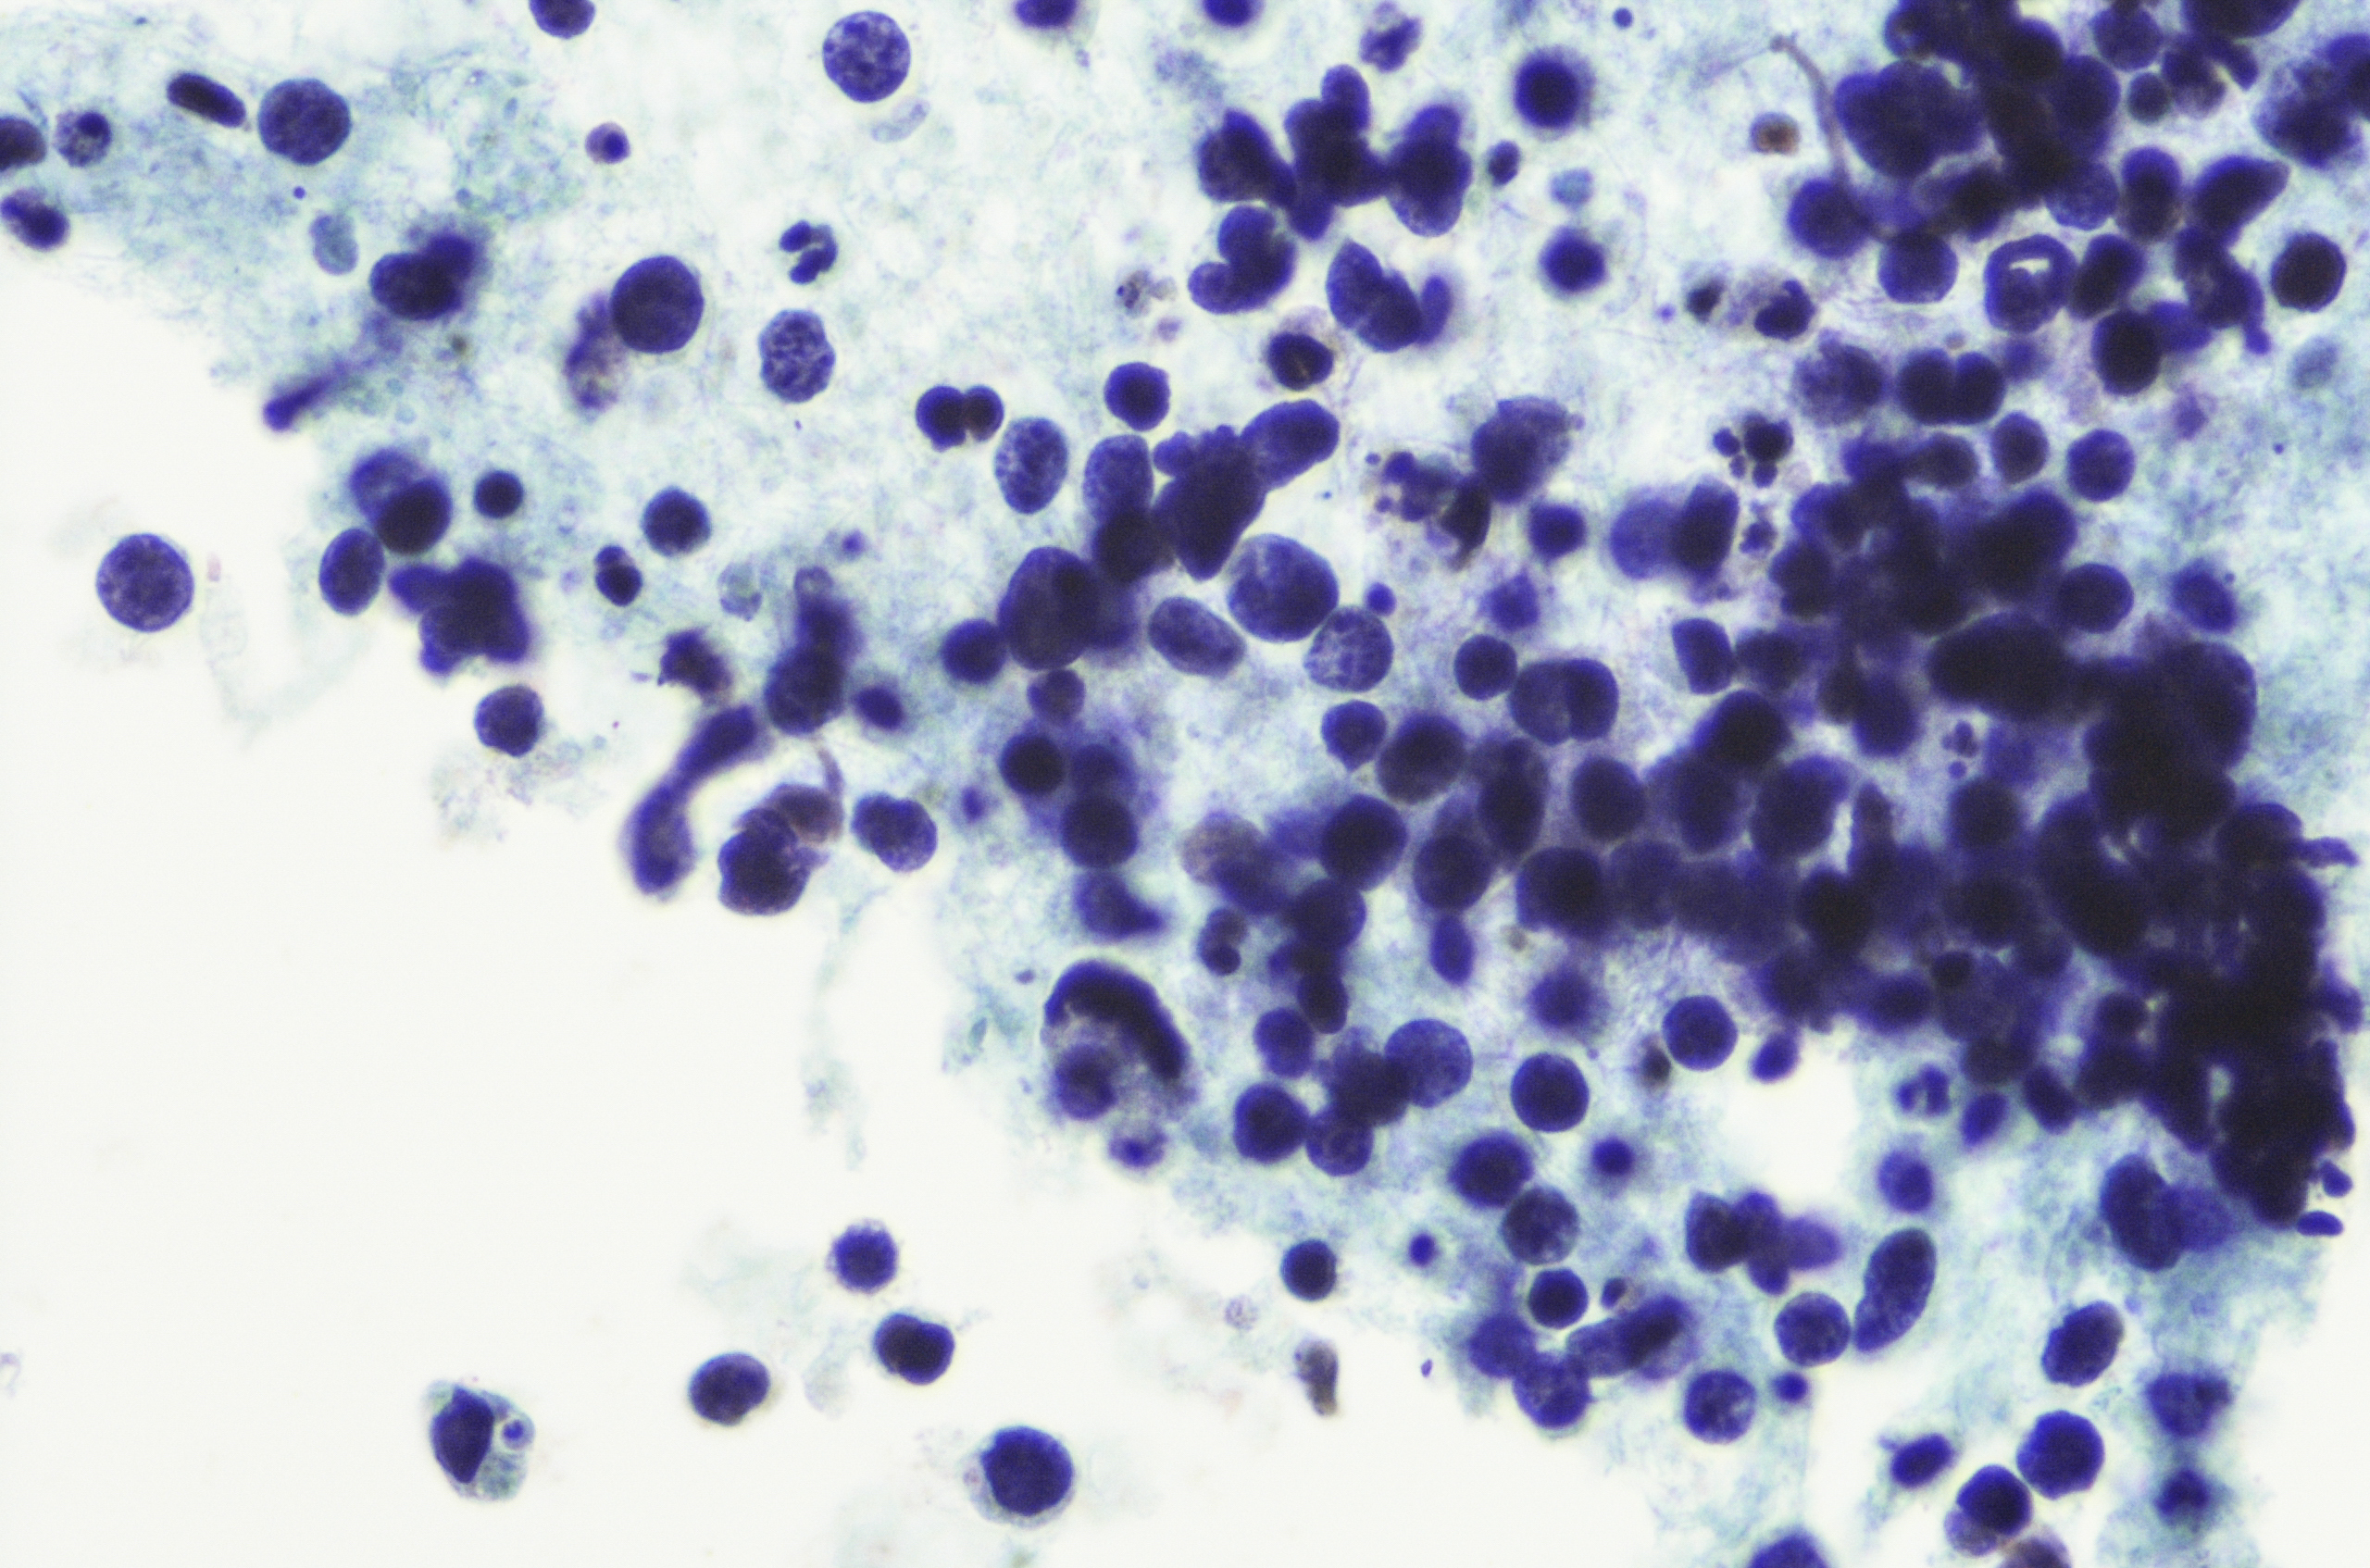

The most common type of lung cancer is called non-small cell lung cancer. Non-small cell lung cancers include, squamous cell carcinoma that starts in the cells that line the airways of the lungs, adenocarcinoma the most common type of non-small cell lung cancer starting the mucous-secreting lung cells or large cell carcinoma.

The other type of lung cancer is called small cell lung cancer, which usually starts in the bronchi, and grows and spreads to other parts of the body quickly.